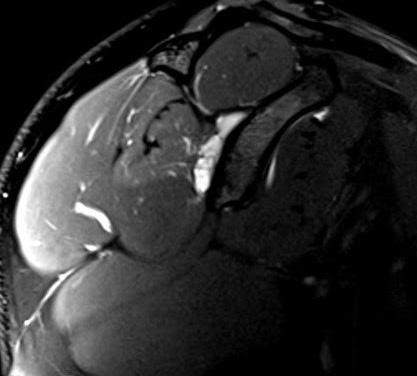

QUISTE PARALABRAL POSTERIOR

ASOCIADO A POSIBLE COMPRESIÓN DEL NERVIO

SUPRAESCAPULAR Y DENERVACIÓN DEL INFRAESPINOSO

DATOS CLÍNICOS:

Paciente masculino de 35 años de edad que acude para valoración por dolor persistente en hombro derecho, con antecedente de subluxación glenohumeral posterior. Refiere dificultad progresiva para realizar movimientos de rotación externa y debilidad en actividades por encima de la cabeza. Se realiza artro-resonancia magnética con contraste.

ESTUDIO REALIZADO:

Artroresonancia magnética de hombro derecho con resonador de 1.5T. Se inyectaron 15cc de medio de contraste intraarticular bajo guía ecográfica en el receso articular posterior, obteniendo imágenes multiplanares en secuencias T1-FS, DP-FS y volumétricas T2-me3D.

Figura 1: Secuencia sagital T1-FS: adecuada distensión de la cápsula articular tras la administración directa de medio de contraste bajo guía ecográfica.

HALLAZGOS RELEVANTES:

Se identifica un quiste paralabral lobulado de 3.4 x 2.3 cm en la escotadura espinoglenoidea, sin comunicación aparente con la articulación glenohumeral.

El vientre muscular del infraespinoso muestra incremento de señal miofibrilar, ligeramente mayor al estudio previo, lo cual sugiere cambios por denervación.

Se observa una rotura basal incompleta del labrum glenoideo tipo SLAP VIII, que se extiende de las 7 a las 3 en sentido horario, lo cual probablemente generó el quiste.

Figura 2: Secuencia axial PD-FS: quiste bilobulado en la escotadura espinoglenoidea.

Este tipo de lesión debe distinguirse de las neuropatías primarias o por atrapamiento mecánico sin masa. El hallazgo de un quiste no comunicante con signos de denervación refuerza la hipótesis de compresión secundaria a la lesión labral, con potencial beneficio quirúrgico si se confirma la sintomatología asociada.

CONCLUSIÓN / APRENDIZAJE CLAVE:

Los quistes paralabrales en la escotadura espinoglenoidea deben evaluarse cuidadosamente ante la sospecha de neuropatía del nervio supraescapular, ya que su compresión puede causar denervación progresiva del infraespinoso, con repercusiones funcionales significativas.

Subluxación posterior de la cabeza humeral con condrosis grado 4 y cuerpo libre osteocondral en el espacio subcoracoideo.

DIAGNÓSTICO Y DISCUSIÓN:

Se trata de un caso de quiste paralabral posterior en la escotadura espinoglenoidea, secundario a una rotura labral basal, sin comunicación con la cápsula articular y con signos incipientes de denervación del músculo infraespinoso, lo cual sugiere compresión extrínseca del nervio supraescapular.

El nervio supraescapular transcurre por la escotadura espinoglenoidea y está en estrecha relación con los quistes paralabrales posteriores. La presencia de un quiste de gran tamaño puede generar compresión crónica, provocando dolor, debilidad y atrofia muscular progresiva, especialmente del infraespinoso, lo cual concuerda con los hallazgos clínicos y de imagen.

3:

Figura

Secuencia sagital PD-FS: incremento difuso de la señal miofibrilar del músculo del infraespinoso por probable denervación.